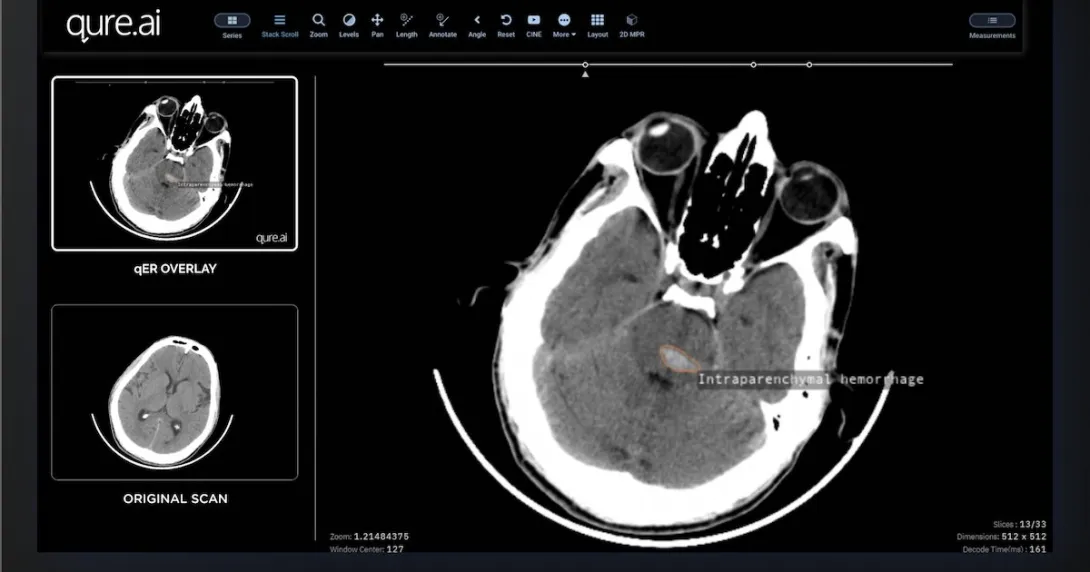

Interface of the Qure.ai qER software

Photo courtesy of Qure.ai

Qure.ai offers AI solutions that help streamline the stroke care pathway. One of its flagship products, qER, delivers quick reading and interpretation of heart CT scans with a turnaround time of two minutes. This information is then stored on the Qure app, a mobile platform that can connect all multidisciplinary teams from different hospitals.